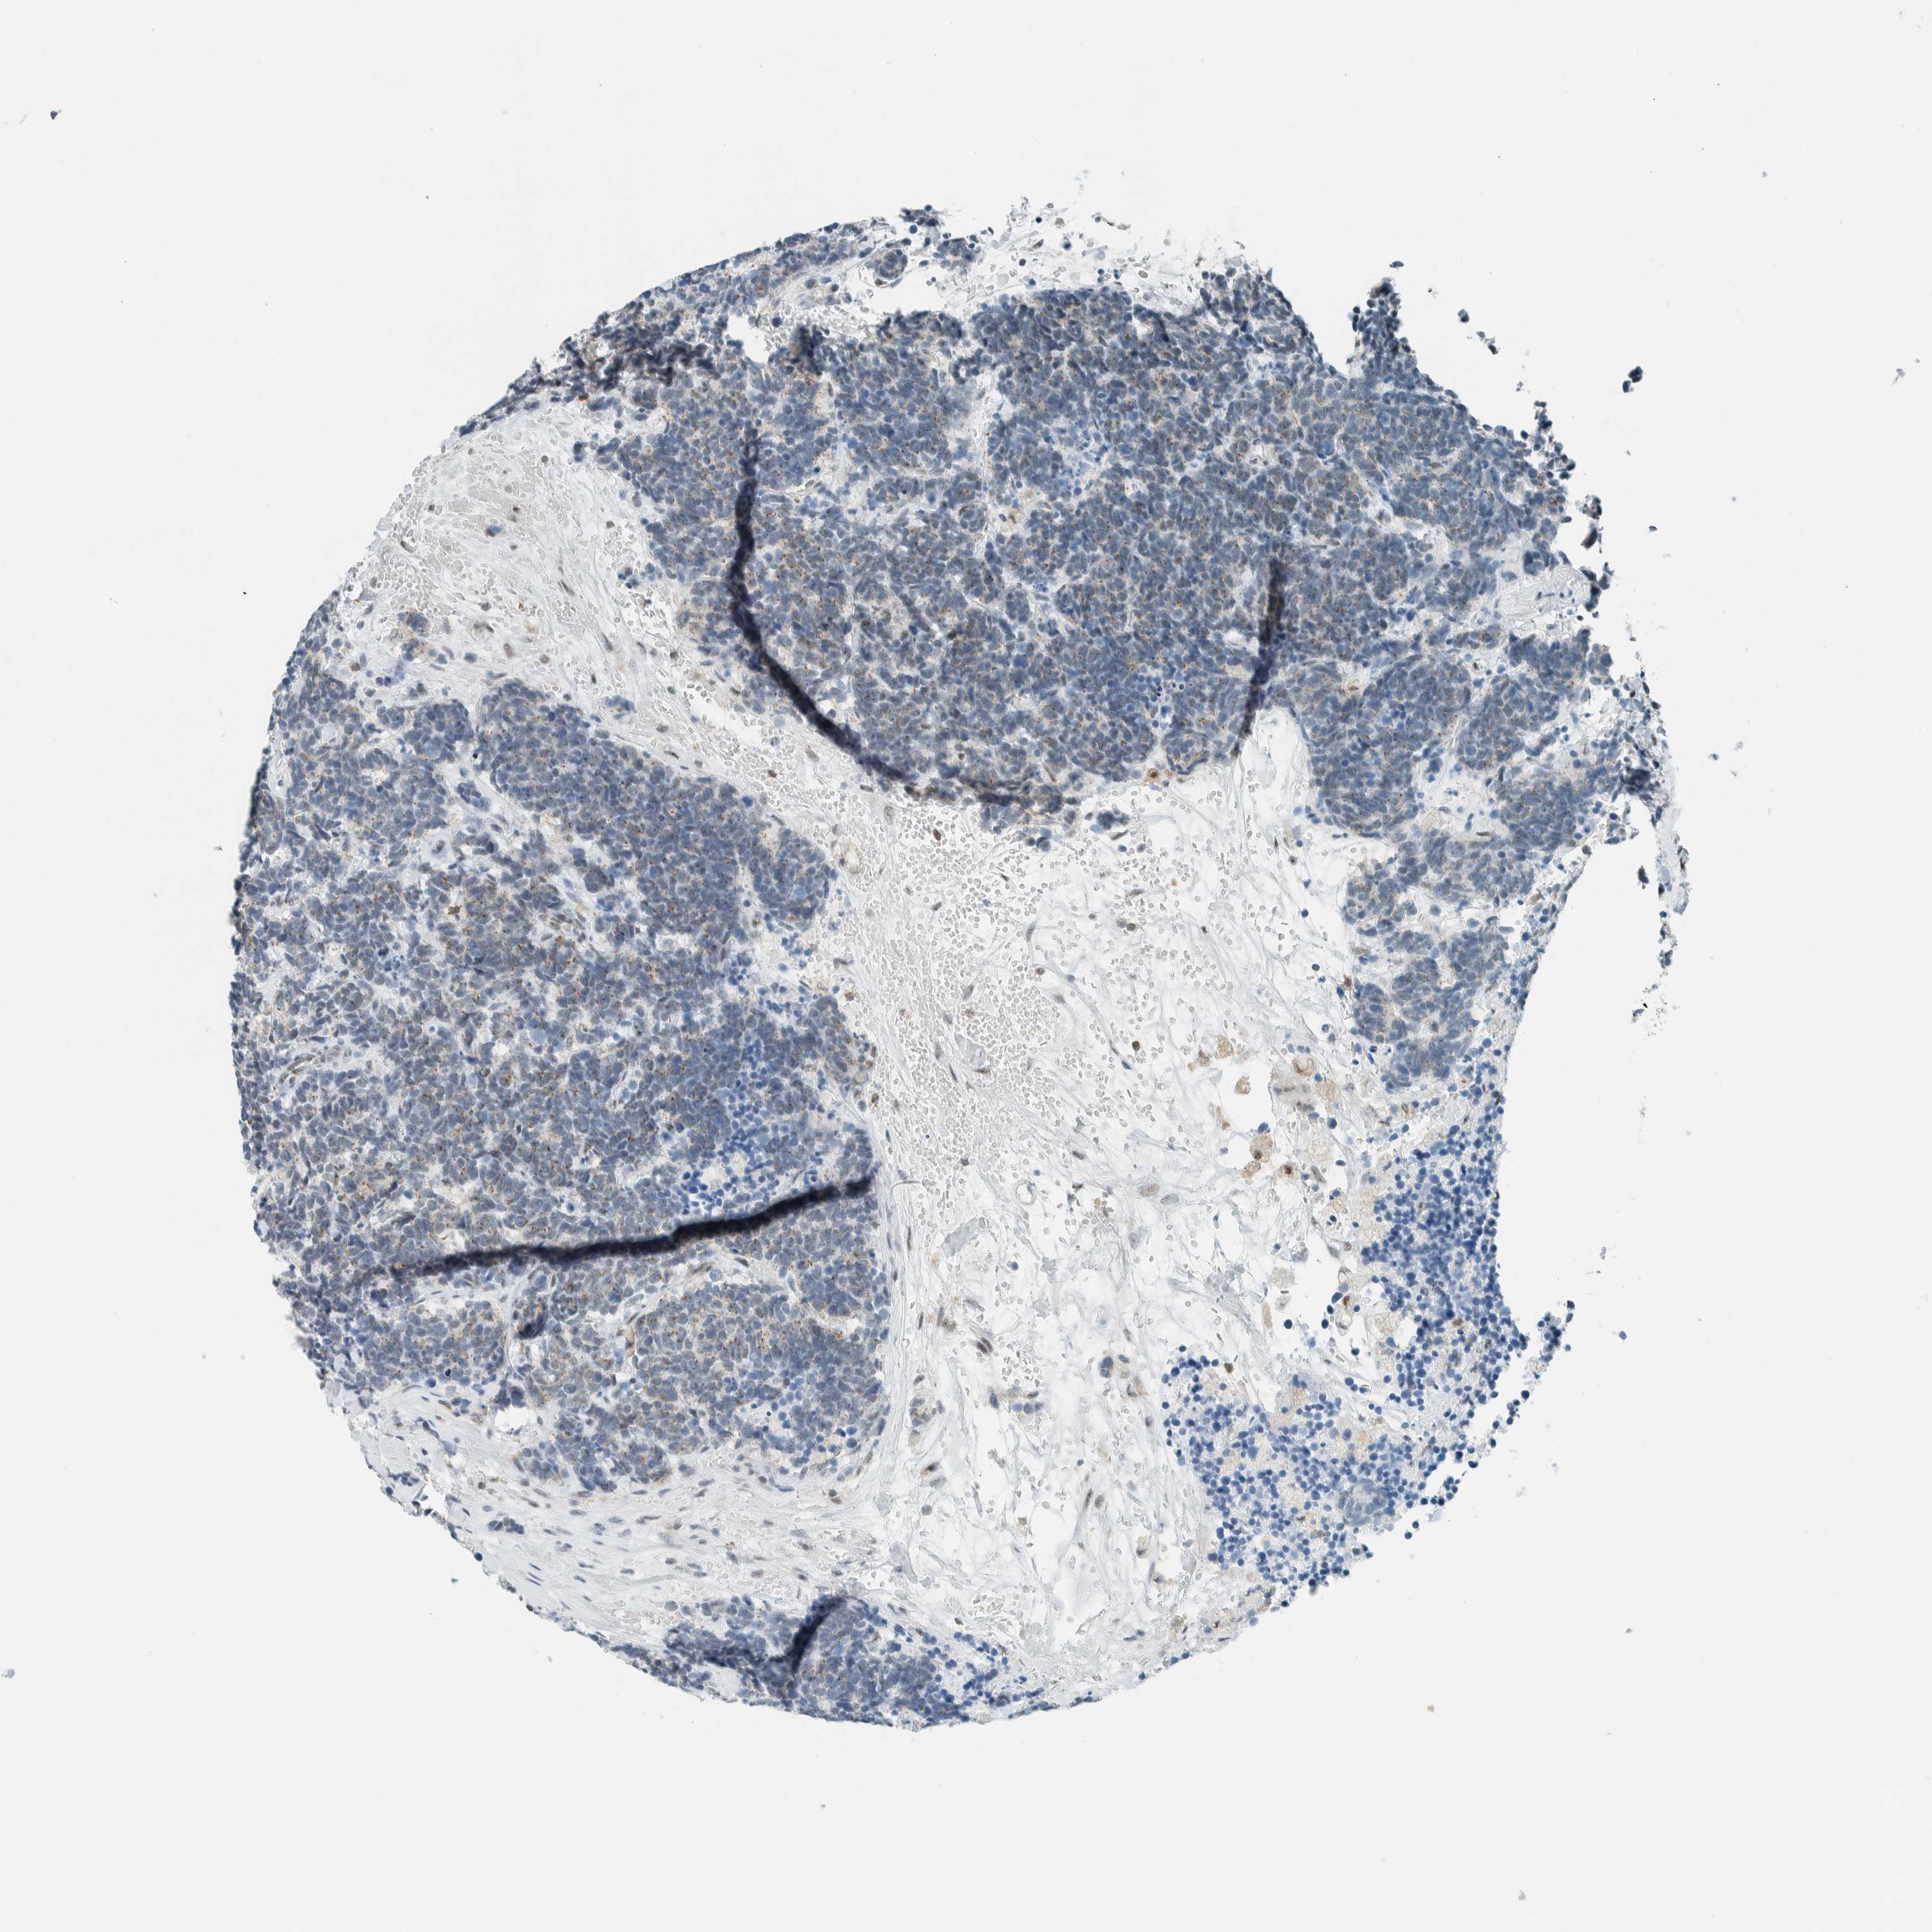

CARCINOID - Protein expressioni

A mouse-over function shows sample information and annotation data. Click on an image to view it in a full screen mode. Samples can be filtered based on level of antibody staining by selecting one or several of the following categories: high, medium, low and not detected. The assay and annotation is described here.

Each image is clickable and will lead to virtual microscopy that enables deeper exploration of all samples and also displays staining intensity scores, fraction scores and subcellular localization as well as patient and tissue information for each sample.

Antibody HPA021883

Antibody HPA021886

Staining

High

Medium

Low

Not detected

Intensity

Strong

Moderate

Weak

Negative

Quantity

>75%

75%-25%

<25%

None

Location

Nuclear

Cytoplasmic/membranous

Cytoplasmic/membranous,nuclear

Carcinoid, malignant, NOS

Carcinoma, NOS